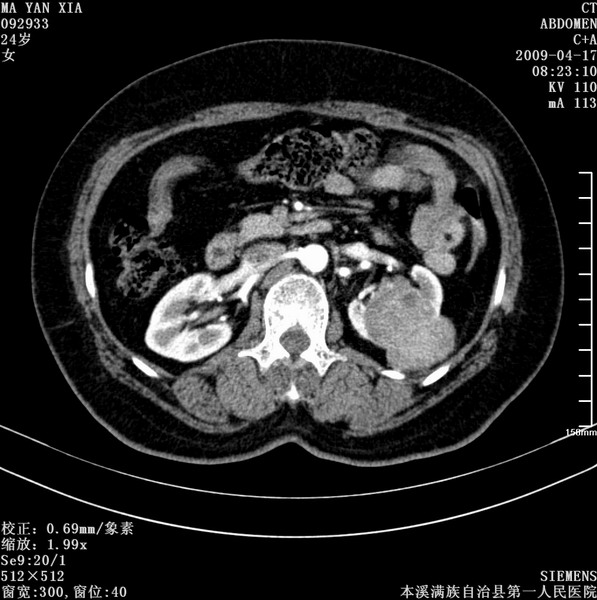

标题: CT19443:肾脏肿瘤两个区强化不一样。 [打印本页]

标题: CT19443:肾脏肿瘤两个区强化不一样。

女,51岁,体检时发现肾脏占位,建议ct增强。无任何自觉症状。

典型的不均匀强化,左肾癌